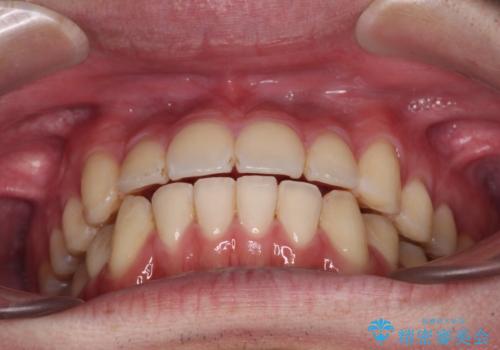

八重歯と前歯のクロスバイト ワイヤー装置で短期間矯正

治療開始の頃は、食事や歯磨きが慣れず、装置が頻繁に脱落しましたが、2,3ヶ月ほどで慣れ、その後は1年ほどで治療を終えることができました。